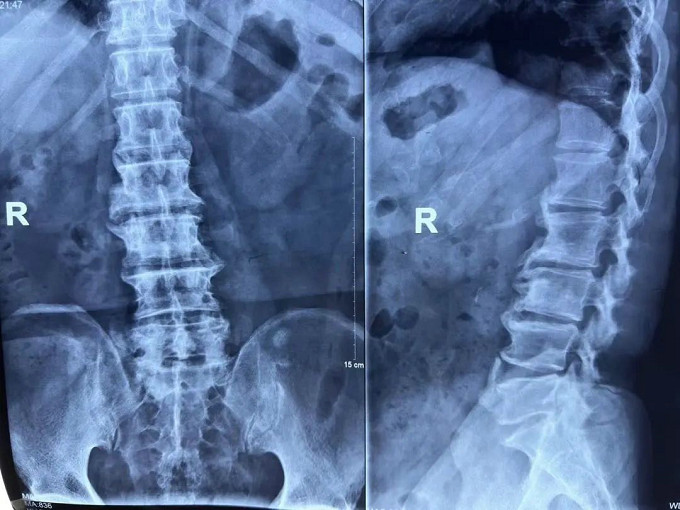

術(shù)前

X線片

可以明顯的看出,患者術(shù)前椎間盤突出壓迫到了神經(jīng)。